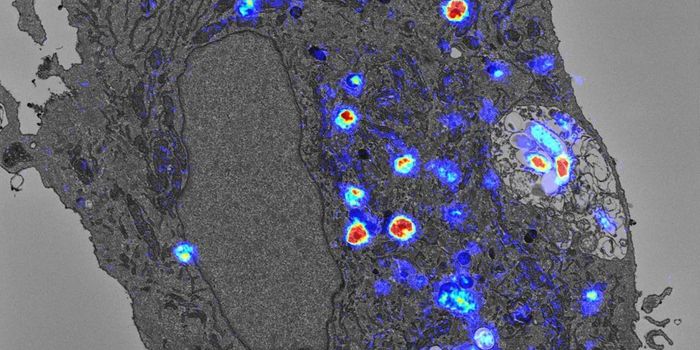

APR 04, 2022Cell & Molecular BiologyAbout 1.5 million new HIV infections are thought to have occurred last year, and while COVID-19 has dominated concerns a ...

FEB 21, 2022Cell & Molecular BiologyTwo people have been cured of HIV, and now, a US woman joins them. In this third case, stem cell transplants were being ...